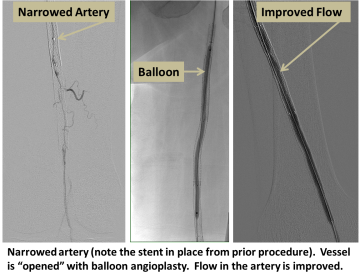

The artery is accessed with a small puncture, and the area of blockage is crossed using specialized wires and catheters. The blockage is then opened using balloon inflation (angioplasty), flexible metallic tubes (stents), or by directly removing the atherosclerotic plaque (atherectomy).